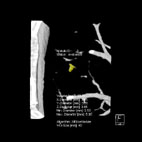

經放大後發現其為長3.85mm寬3.15mm的小結節(左圖),可協助專科醫師進行進一步診斷。